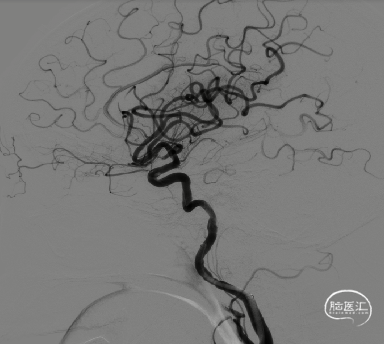

8F导引导管在多功能管及泥鳅导丝导引下直接进入右侧颈总动脉,此时Skathi远端通路导管尾端连接自制50ml负压注射器一路裸奔抽吸至C5段,反复抽吸3次,抽出大量血栓,回血通畅后,轻轻冒烟提示颈内动脉通畅,大脑中动脉M1远端闭塞,与取栓前后循环造影显示情况一致。

大脑中动脉M1段血栓采用SWIM技术-抽拉结合,避免血栓逃逸。

一次SWIM取栓,成功血管再通,达到mTICI分级:3级。